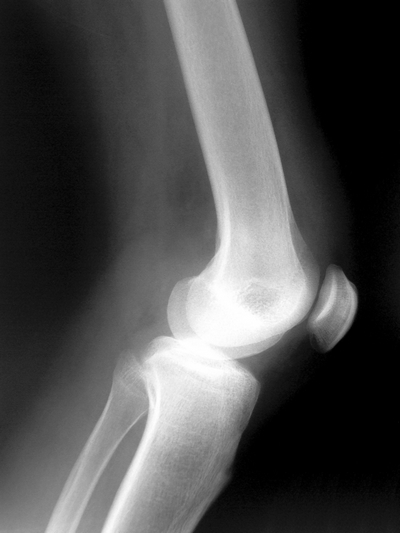

visão lateral da articulação do joelho - radiografia